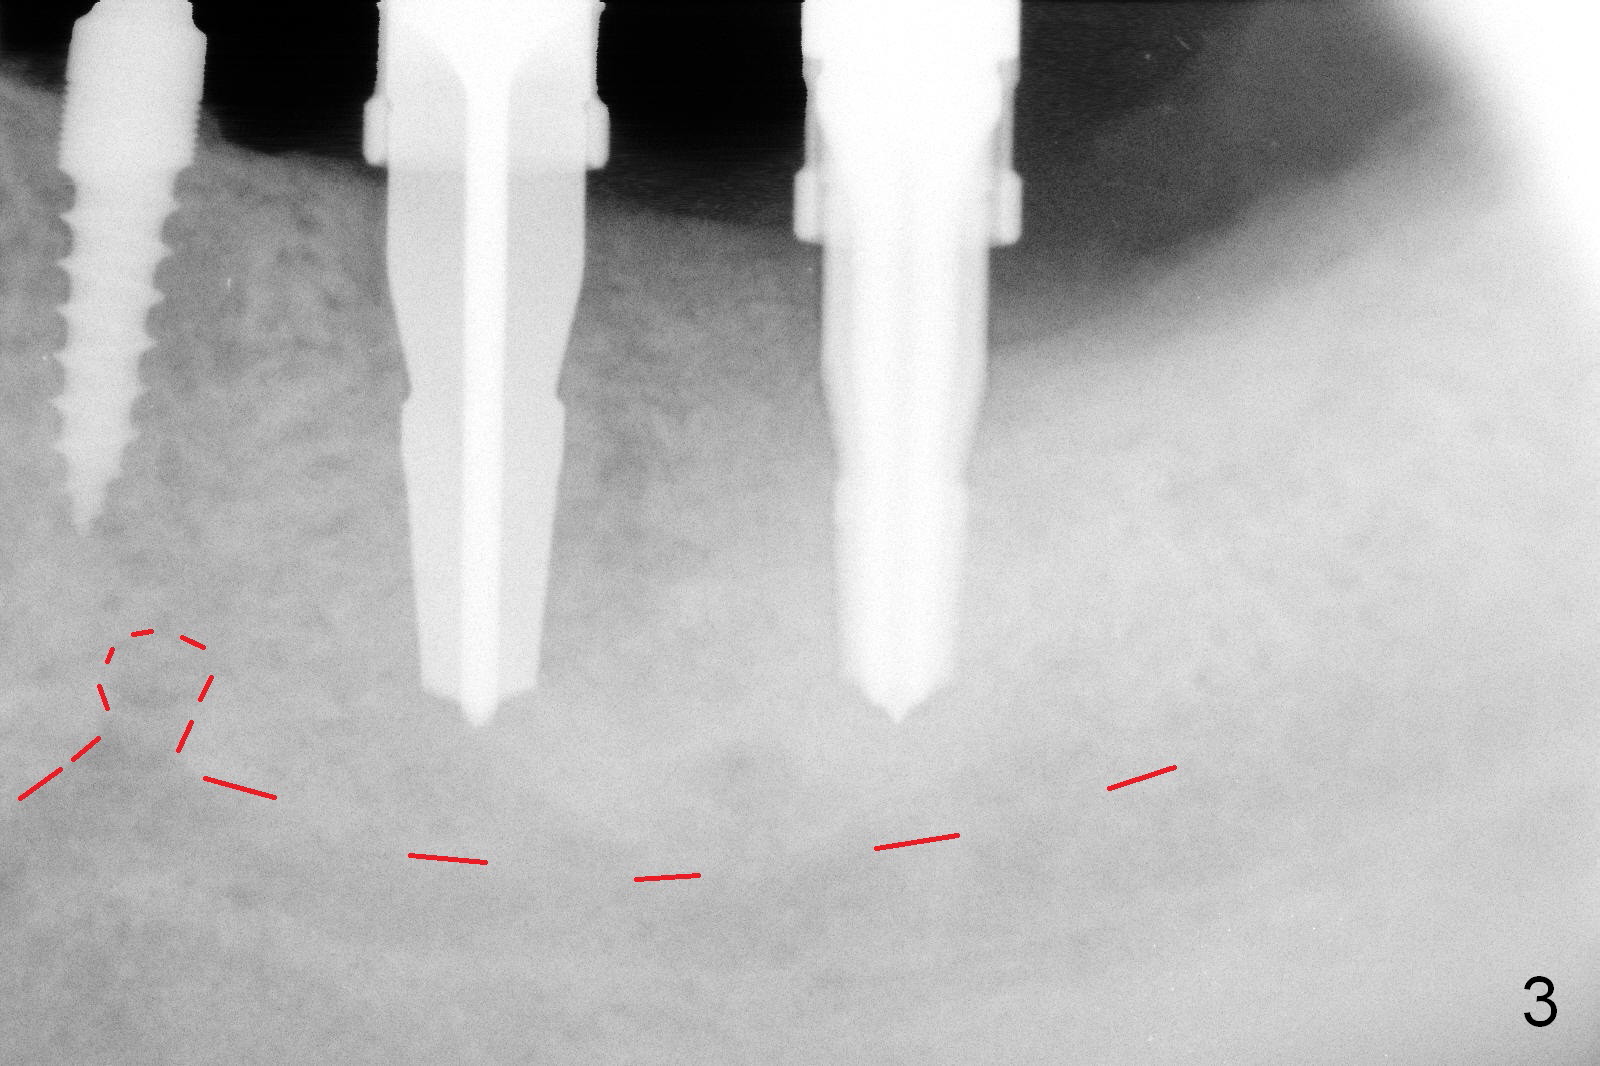

A 3x11 mm 1 piece implant is placed at the site of #20 with insertion torque > 60 Ncm (Fig.3). When a 4.1x10 and 4.5x12 mm drills are being used at the sites of the #18 and 19, respectively, the buccal and lingual crestal bone starts to be perforated ~ 2 mm apicocoronally.